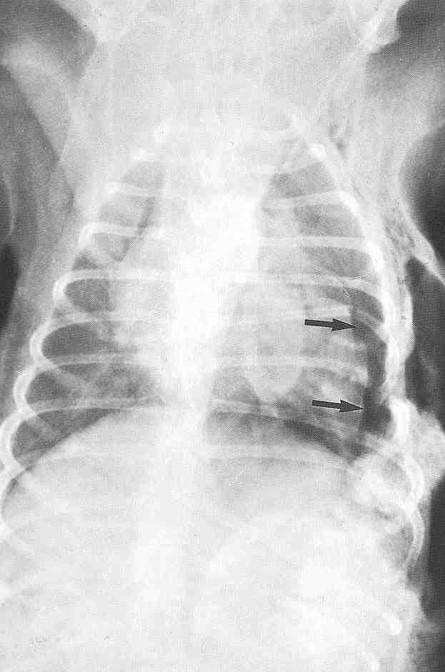

What do these black arrows show?

Pneumothorax